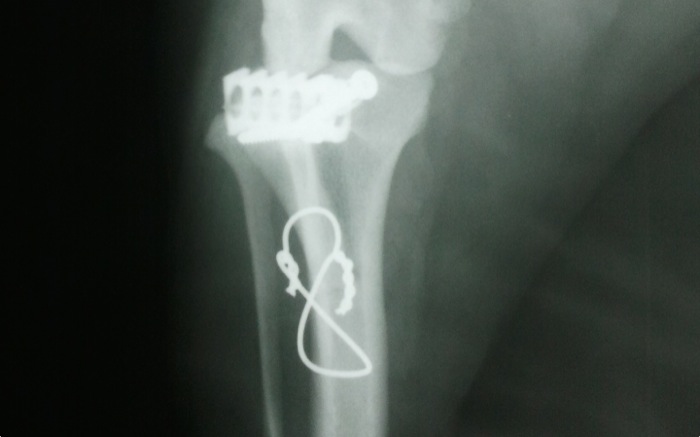

La imagen anteroposterior presenta la banda en ocho y la cesta que está alejada de la superficie articular. El cerclaje según el peso va de 0,8 a 1,2 mm y a este perro de 9,600 kg le corresponde 0,8 ó 1 mm. En este caso se ha utilizado 0,8 mm.

La imagen postquirúrgica es la que se espera salvo que se comprueba una grieta al final de la osteotomía. No era visible en la operación porque quedaba bajo el periostio y no debe influir pero refuerza la opción de poner siempre un cerclaje. Esta técnica es más sencilla sin perder seguridad respecto a las otras que modifican la biomecánica de la rodilla y persiguen una estabilidad dinámica alterando la geometría de la rodilla. Otras opciones que eliminan la función del LCC son: TPLO 1993 tibial plateau levelling osteotomy, TTO triple tibial osteotomy, TTA 2002, tibial tuberositty advancement y la primera de 1984 con la TWO, tibial wedge osteotomy.